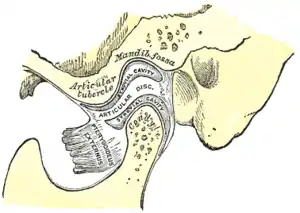

Sagittal section of the temporomandibular joint (labeled as "pterygoideus externus", visible in gray at bottom right) | |

The upper/superior head originates on the infratemporal surface and infratemporal crest of the greater wing of the sphenoid bone and inserts onto the articular disc and fibrous capsule of the temporomandibular joint.

The primary function of the lateral pterygoid muscle is to pull the head of the condyle out of the mandibular fossa along the articular eminence to protrude the mandible. A concerted effort of the lateral pterygoid muscles helps in lowering the mandible and opening the jaw, whereas unilateral action of a lateral pterygoid produces contralateral excursion (a form of mastication), usually performed in concert with the medial pterygoids.